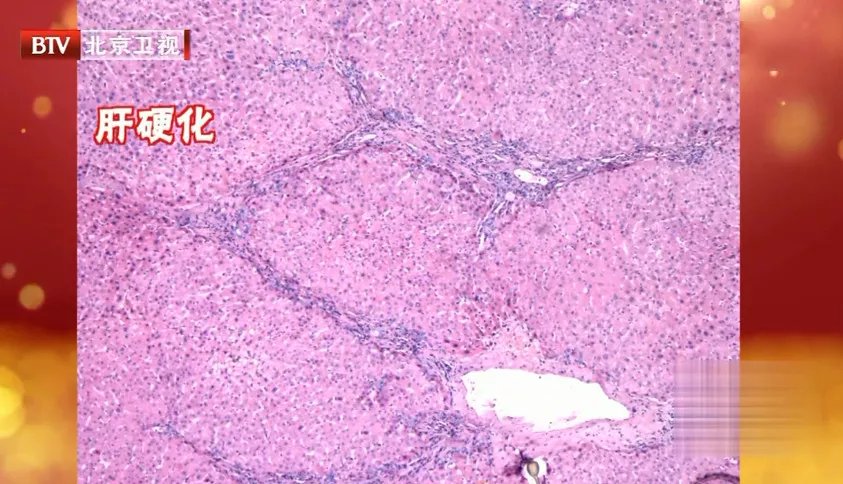

③随着病情的发展,炎症继续发作,刺激肝脏内纤维组织增生并逐渐加厚变硬,即肝硬化。此时,肝功能损害很严重了,肝脏可能因肿胀而增大,也可能会萎缩。再恶化下去就是肝癌。